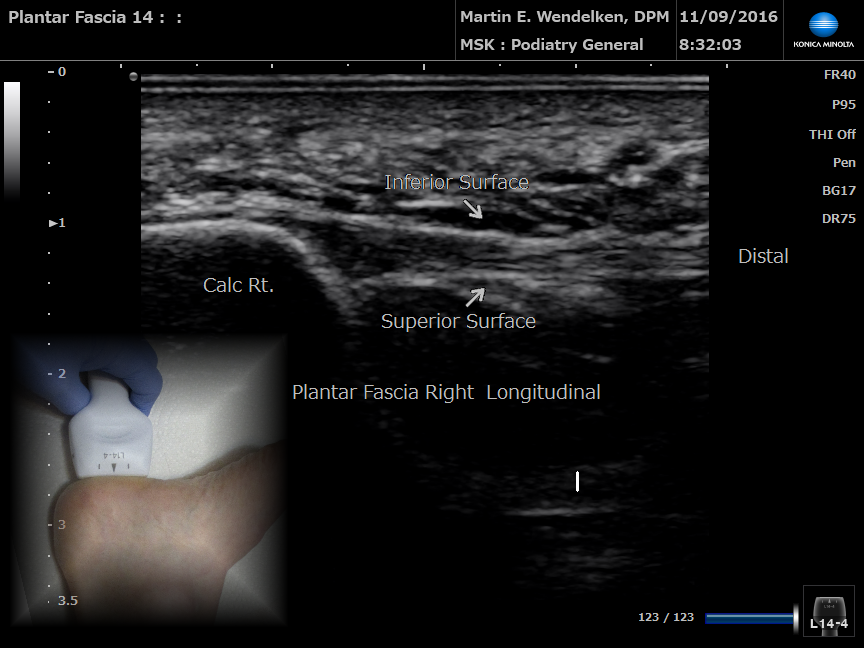

• Image 4: Plantar Fascia Tear